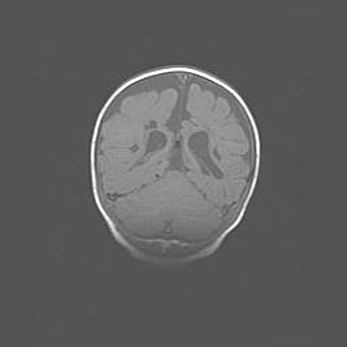

Подострая гематома правой гемисферы мозжечка.

Наружная гидроцефалия.

Возраст: 15 дней

Вес: 3100 г

Пол: женский

Окружность головы: 37 см

Срок гестации: 35-36 недель

При открытой наружной форме гидроцефалии у новорожденных расширяются и переполняются субарахноидные пространства.

Кровоизлияния в мозжечок имеют две клинико-анатомические формы: полушарные гематомы и кровоизлияния в червь.

К появлению этой патологии может привести: повреждения головного мозга, возникающие в результате асфиксии и гипоксии плода при беременности, или травмы во время родов. Редко гематома мозжечка может быть результатом первичной коагулопатии и сосудистой мальформации, диссеминированном внутрисосудистом свертывании, изоиммунной тромбоцитопении.